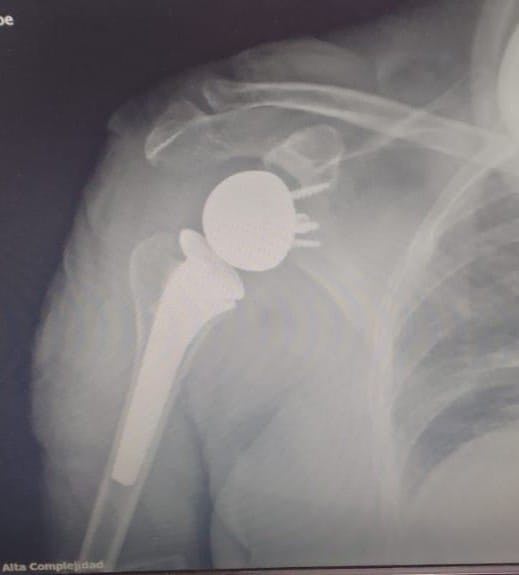

A pocos días de finalizar el 2024, el Hospital de Alta Complejidad “Pte. Juan Domingo Perón”, sigue consolidando su prestigio con importantes logros. Recientemente, el Servicio de Traumatología realizó con éxito la primera cirugía de prótesis reversa de hombro, un avance significativo que reafirma su compromiso con la excelencia médica y la innovación.

Este procedimiento innovador marca un hito en el sistema de salud, permitiendo una mejora significativa en la calidad de vida de pacientes con patologías severas de hombro. La operación fue realizada por la Subespecialidad de Hombro y Codo.

Cabe destacar que la prótesis reversa de hombro es una técnica avanzada que se utiliza en casos de artropatía por desgarro del manguito rotador o artritis severa, cuando los tratamientos convencionales ya no son efectivos.

Esta cirugía busca devolver la movilidad del hombro utilizando otros músculos prescindiendo del manguito rotador y quitar el dolor.

En este caso la paciente intervenida, de 78 años sufría de una lesión masiva e irreparable de manguito rotador con desgarro y degeneración grasa de los músculos. La misma permaneció solo un día internada y obtuvo su alta médica satisfecha con ejercicios instruidos de movilización del hombro.